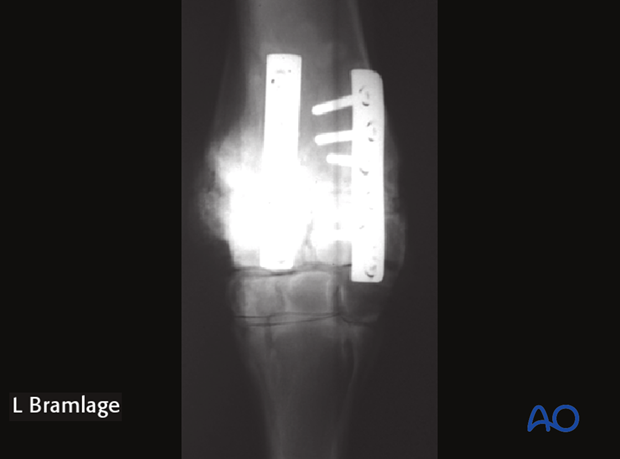

The plates are normally located craniomedially and craniolaterally over the intermediate and radial carpal bones of the proximal row. Occasionally, the plates will be placed over the intermediate and ulnar carpal bones if marked realignment of the limb is necessary.

For an antebrachial carpal joint arthrodesis, the medial plate is attached to the radius first and extended distally onto the radial carpal bones.

Once the plate is attached proximally the tension device is attached to the distal end of the plate and used for compression across the osteotomy site. Normally only the first plate requires use of the tension device. Axial compression with the second implant can be achieved by using the dynamic compression holes. If no osteotomy is present and significant reduction of a deformity is not necessary the dynamic compression capabilities of the implant may be sufficient to achieve compression across the joint to be fused.

Once sufficient compression is achieved using the tension device in the first plate, the remaining screws are inserted into the radial carpal bones.

Radiographs are taken after all screws are inserted to assure that all screws are in the proper location and the joint is been well reduced.